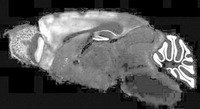

探索一个新笼子在转基因小鼠大脑中形成了氯氮平受体。用药物激活这些受体又重新唤醒了这些记忆。

在第一项研究中,美国加利福尼亚州圣地亚哥市斯科利普斯研究所的细胞生物学家Mark Mayford和同事,在注射了精神分裂症药物氯氮平后,使转基因小鼠重温了一段记忆。某些活动,例如探索一个新的环境,会让这些小鼠产生针对药物的受体;当它们随后被注射药物后,相同的神经细胞又像小鼠探索新环境时那样被点燃。

而在发表于《自然》杂志的第二项研究中,研究人员也恢复了小鼠的一段过去的记忆。在这项研究中,诺贝尔奖得主、美国剑桥市麻省理工学院(MIT)的分子生物学家Susumu Tonegawa和同事,在名为海马体的一组记忆关联细胞中添加了一种光敏受体。这些细胞已知与恐惧的认知有关。这些小鼠与第一项研究一样也经历了电击的过程,随后它们被送回自己的笼子。当这些受体被一束激光脉冲激活后,这些啮齿动物立刻僵住了——尽管没有任何线索、视觉或其他方式提醒它们电击的发生。Tonegawa说:“我们的发现表明,激活这些细胞绝对足以引发小鼠的回忆。”